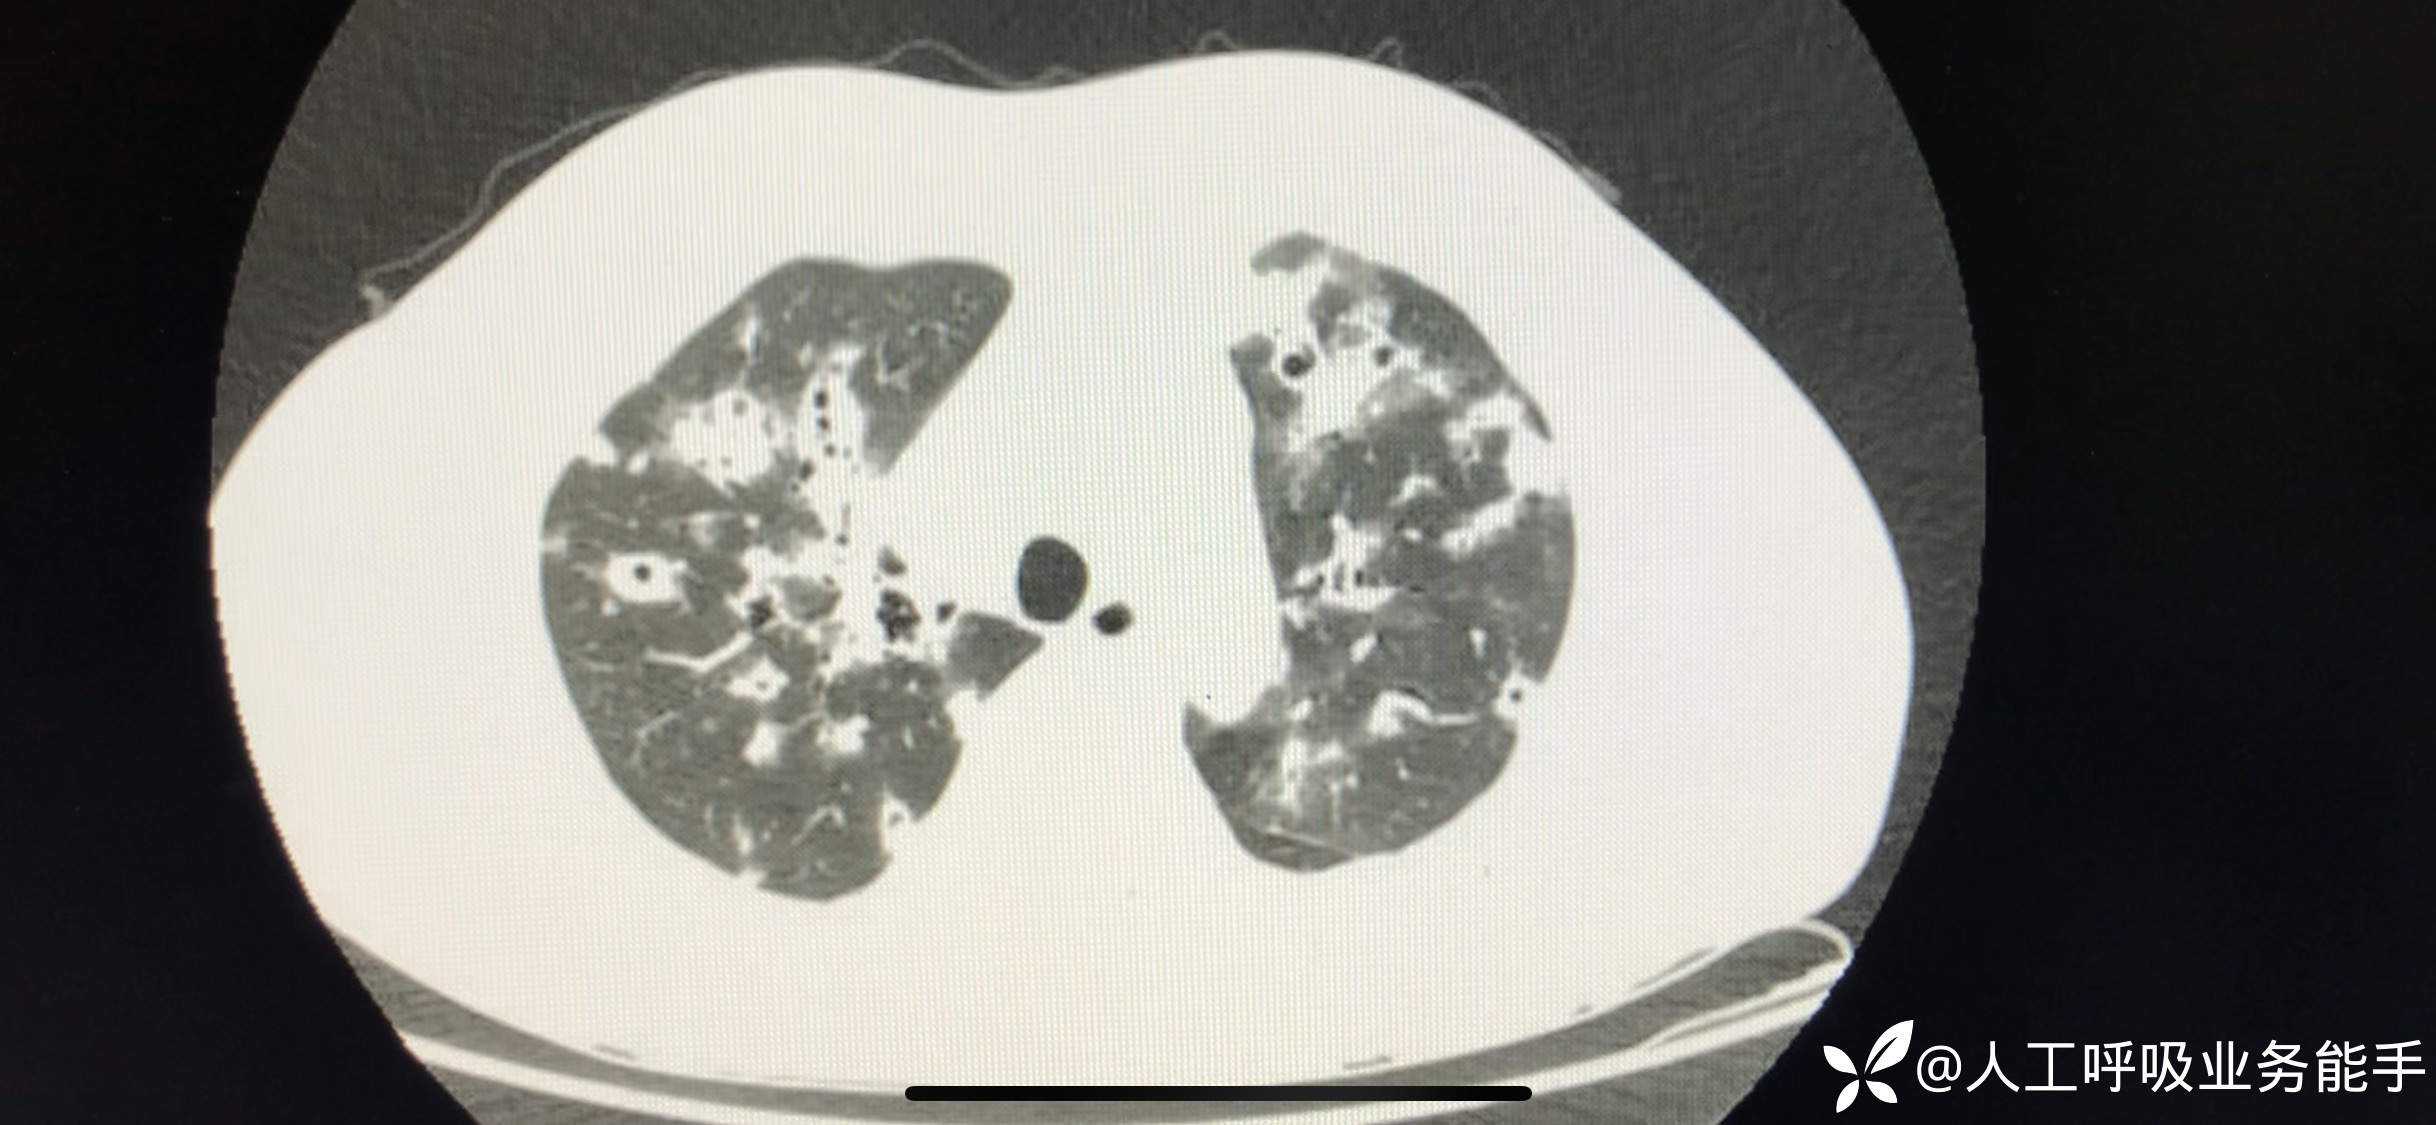

初诊影像: